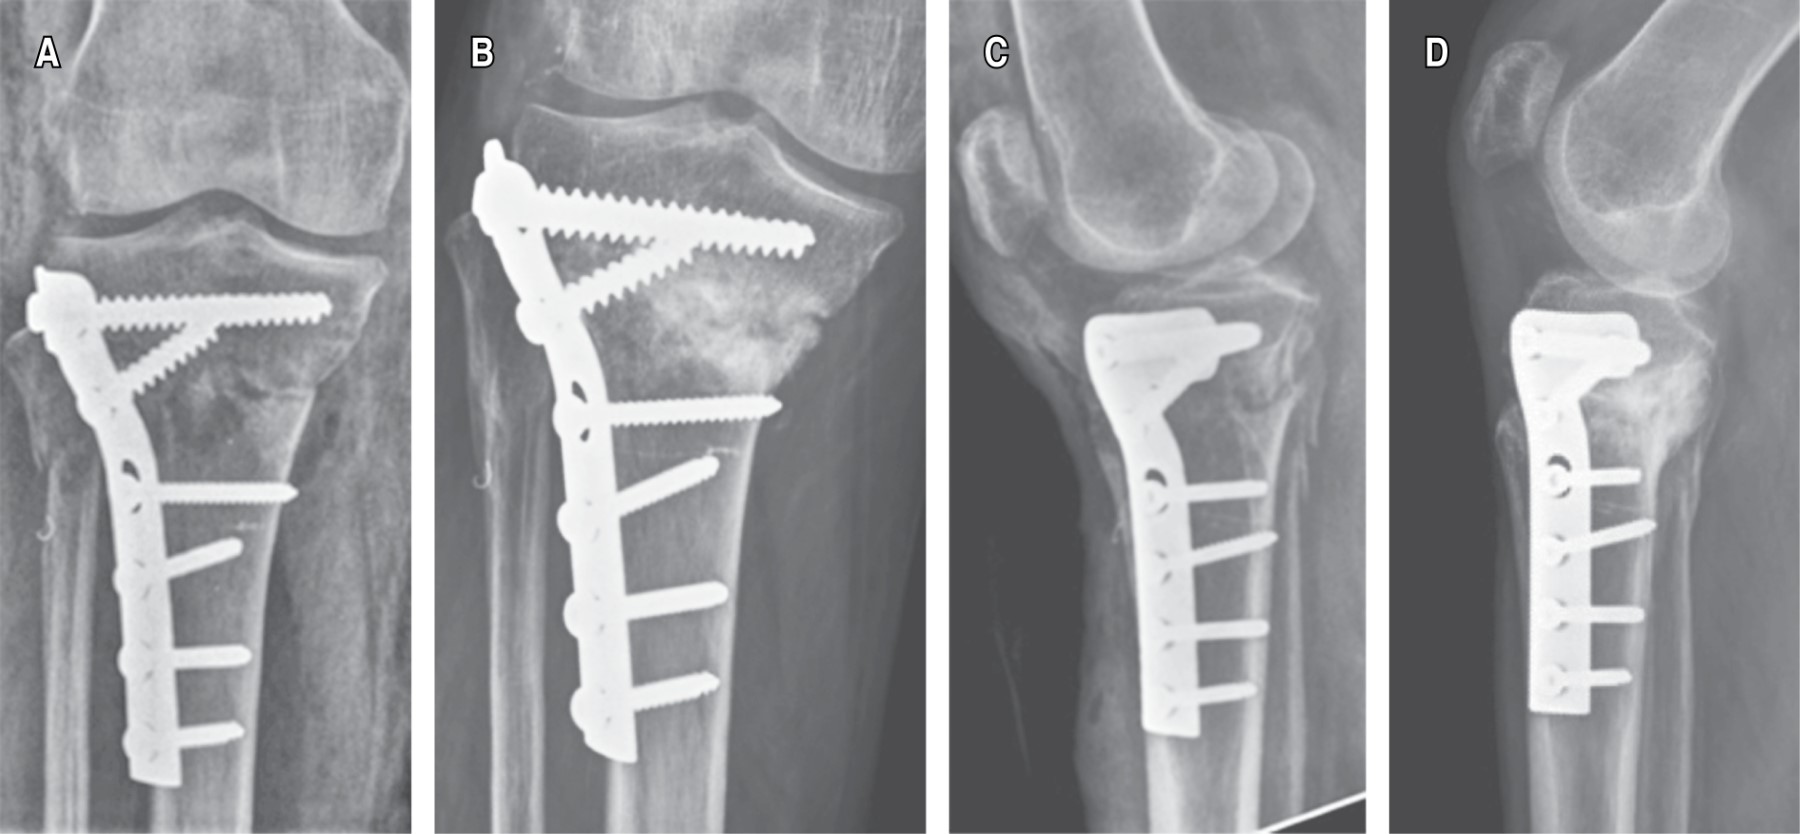

GRUPO 2 (FIGURA 3) DESPLAZAMIENTO MPTA Y PPTA DURANTE SEGUIMIENTO

Se observó un mayor desplazamiento en el plano coronal (MPTA) y sagital (PPTA) con disminución en la magnitud de ambas mediciones debido a colapso durante el seguimiento, además de obtener reducciones con valores angulares más alejados de los rangos de normalidad para una tibia intacta. Esto puede ser atribuible a la mayor dificultad para lograr una reducción anatómica cuando se realiza reducción indirecta (Tabla 1).